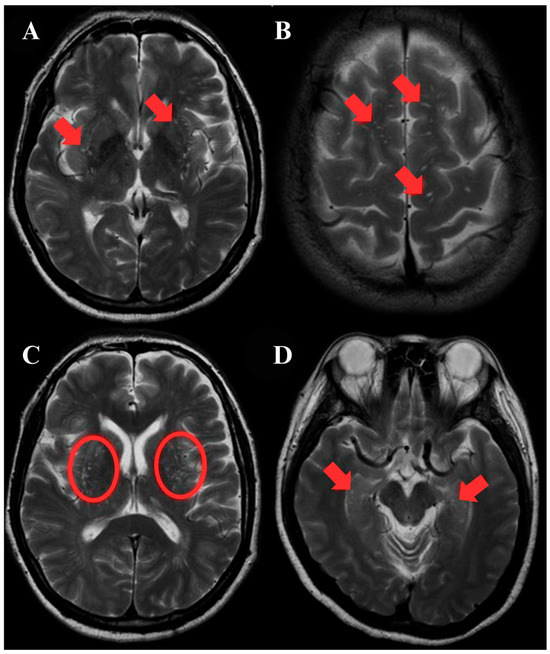

Introduction: Hypertrophic olivary degeneration (HOD) is a rare form of trans-synaptic degeneration involving the Guillain–Mollaret triangle, characterized by enlargement of the inferior olivary nucleus—unlike the atrophy typical of most neurodegenerative processes. It is usually associated with stroke, surgical injury, or demyelination, but [...] Read more.

Introduction: Hypertrophic olivary degeneration (HOD) is a rare form of trans-synaptic degeneration involving the Guillain–Mollaret triangle, characterized by enlargement of the inferior olivary nucleus—unlike the atrophy typical of most neurodegenerative processes. It is usually associated with stroke, surgical injury, or demyelination, but rarely follows hemorrhage from a cavernous malformation (CM). This report presents a case of HOD secondary to a mesencephalic CM hemorrhage, with emphasis on imaging findings and diagnostic considerations. Case Description: A 55-year-old woman presented with acute-onset, right-sided facial, torso, and limb hypoesthesia, along with gait instability. Neurological examination revealed sensory impairment in the right maxillary (V2) and mandibular (V3) trigeminal territories, as well as diminished pain and temperature sensation throughout the right hemibody. MRI revealed a hemorrhage in the posterior mesencephalon near the left red nucleus, leading to the diagnosis of a CM with an associated venous angioma. She was managed conservatively and improved clinically. Six months later, MRI showed hypertrophy and T2/FLAIR hyperintensity of the left inferior olive, consistent with developing HOD. At 1.5 years follow-up, olivary enlargement had progressed—now consistent with stage 2 HOD—and a bilateral palatal tremor was observed, more pronounced on the right side. DTI revealed asymmetric volume loss in the left brainstem fiber pathways at the level of the medulla oblongata, confirming trans-synaptic degeneration. Conclusions: This case highlights HOD as a rare but important complication of mesencephalic CM hemorrhage. Recognition of its characteristic imaging features—olivary hypertrophy with persistent T2/FLAIR hyperintensity—is essential for accurate diagnosis. DTI supports the trans-synaptic mechanism, helping distinguish HOD from other pathologies and preventing unnecessary investigations. Full article